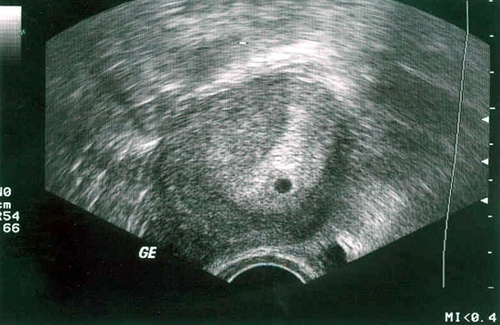

Otrajā nedēļā pēc ieņemšanas ultraskaņas skenēšana joprojām nebūs informatīva. Tas parādīs tikai dzemdes vispārējo gatavību grūtniecībai. Ja šajā laikā uzņemat fotoattēlu no skenera, embrijs izskatīsies kā mazs, melns punkts.